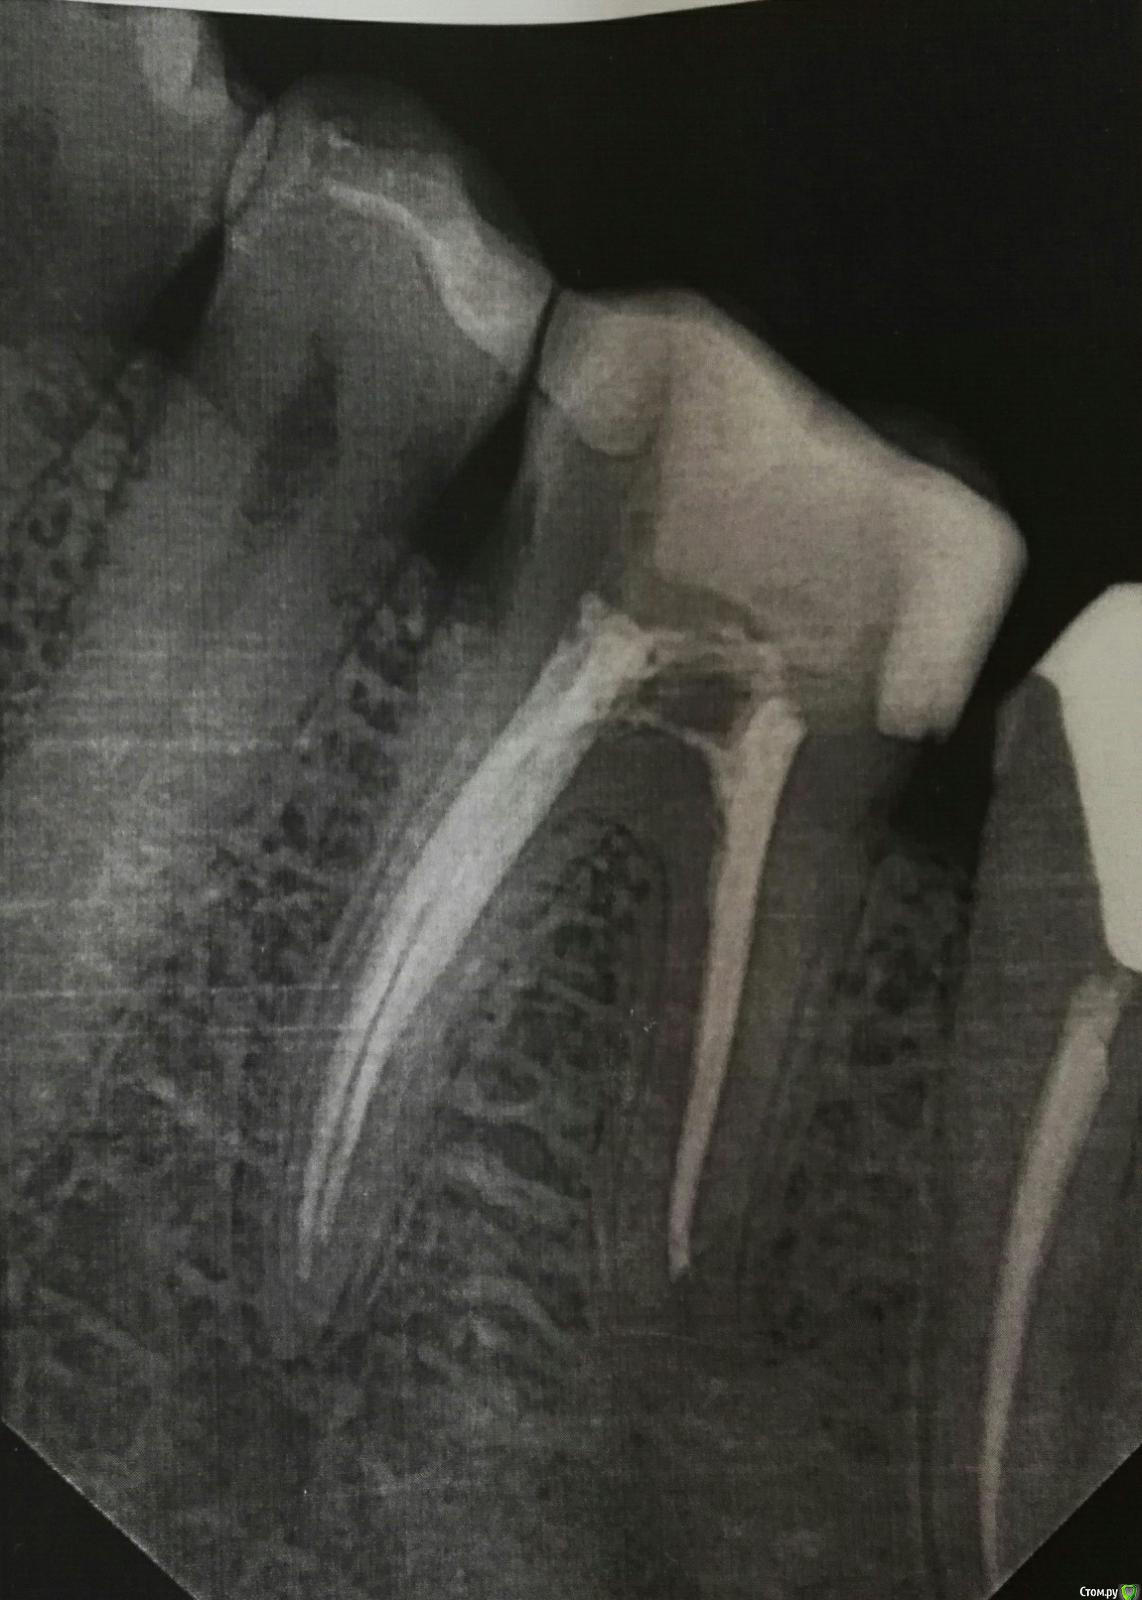

В начале сентября появилась острая пульсирующая боль в 36 зубе. Обратилась в стоматологическую клинику. Во время обработки каналов были обнаружены изменения, который ближе к 37 зубу. Врач положила лекарство на 2 недели. Лимфатические узлы уменьшились, температуры не наблюдалось. Через 2 недели поставили постоянную пломбу и все вернулось, а может даже и увеличились ещё больше. По словам врача, каналы в порядке. Наблюдается боль в процессе чистки зубов и при употреблении твердой пищи. С момента установки постоянной пломбы прошло 1,5 недели. Температура 37,1-37,5.

Прилагаю снимки с сиалографии до лечения и рентген после. Надеюсь на вашу помощь.

Сделайте 3д томограмму есть подозрения на процесс в 3.7 зубе, и точно по датам распишите что когда лечилось и какие были симптомы.